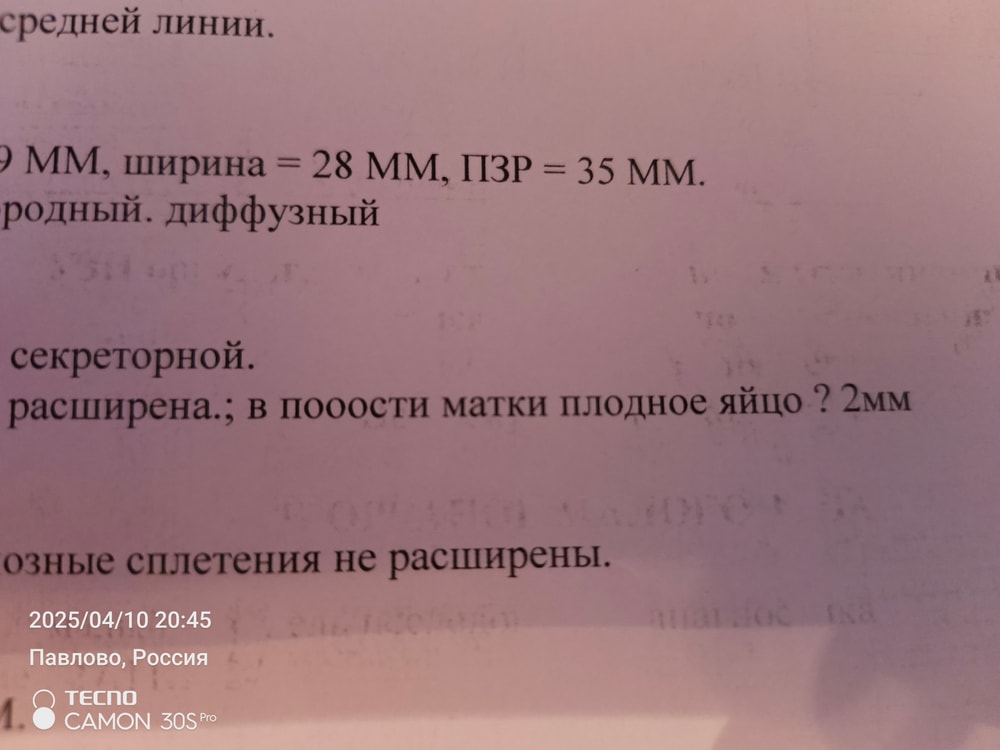

И так начнем чуть с далека, что имеем: 34 года, СПКЯ, 7 лет бесплодия, лишний вес. Муж на СВО мобилизовали в 22 году, соответственно отпуск раз в полгода. Естесно цикл гуляет, овуляция не стабильная. Я знаю что многие начнут писать что как так можно и все дела, но пост не для осуждения, а просто поныть и поддержать. И так сейчас плюс минус 40 день, если пьем дюфастон то цикл 30 дней. Муж уехал с отпуска 30.03. Дюф в том месяце не пила, да просто забила. Овуляция вроде была как я думала по ощущениям, но видать ошиблась. 01.04 делаю тест будьте уверены на дурака, получаю две полоски(естесно бегу на хгч-отрицательный) ну все думаю ладно не судьба мне забеременеть, обговариваю с мужем в отпуске что идем на квоту эко или что-то другое. Параллельно понимаю что надо скинуть 20 кг и в принципе к след отпуску буду готова, заодно сдам все анализы и схожу к репродуктологу. Иду по месту жительства к гинекологу мне выдают список мед центров в СПБ которые работают по омс эко. Выбираю Алмазова, записываюсь, сегодня была на приёме. Все как обычно анамнез собрала, анализы все сдала. Договариваемся с Ре что пью Дюфастон, смотрим овуляцию свою(стимулируемся) Муж приезжает в след отпуск и делаем инсеминацию, если нет идем на Эко. Идем делать с Ре узи, и тут она мне спрашивает когда был Муж, я говорю 30.03 уехал, и показывает мне точку 2 мм в матке. По УзИ вторая фаза, эндометрий серкреторный, но нет ЖТ. То есть ставит по узи беременность малого срока под вопросом, плодное яйцо 2 мм? Сказала ждать 7 дней и идти на ХГЧ, если не придут месячные. Смущает что нет ЖТ. Я конечно пошла взяла первый попавшийся тест в аптеке, думала ну может что-то будет. А там ничего такого и нет 🤷 Вообщем девочки вопрос в чём? Что ждать дальше? И как быть? Идти на хгч ? Я испытала шок, я вышла от нее в полном смятении, так как была уверена что не могу быть беременна. И она испытала небольшой шок от всей ситуации.